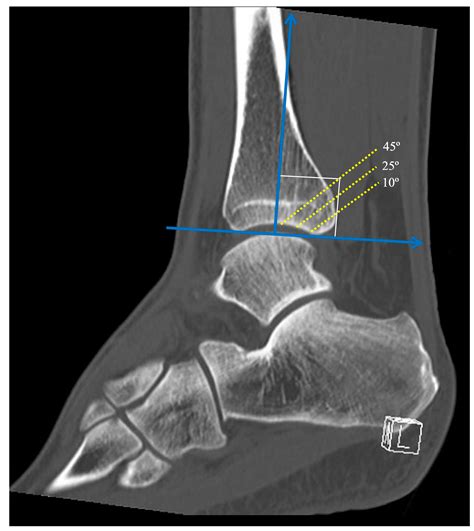

CT Scan Indispensable for assessing the size of the later shard and the degree of articulary surface engagement.

The approach to treatment bet largely on the sizing of the sherd and the constancy of the ankle juncture. Not all break involve or, but when the sherd involves more than 25 % of the tibial articulary surface or if the ankle remains unstable, operative interference is broadly the touchstone of attention.